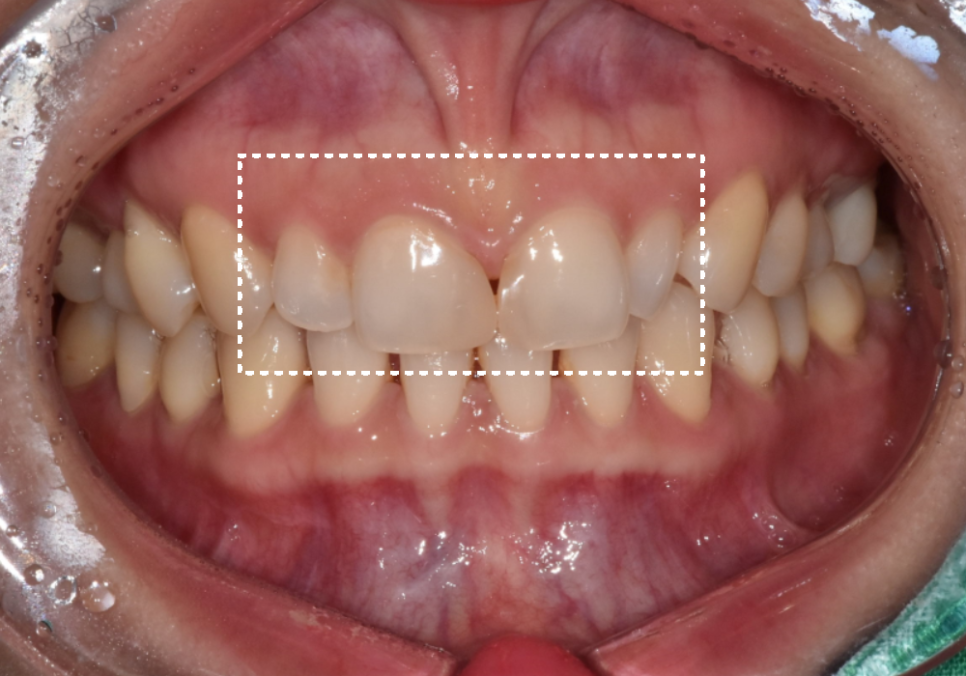

사례1) 서로 다른 앞니 크기 차이로

전체 비율 조정이 필요했던 경우

첫 번째 환자분은

앞니 바로 옆 치아의 크기가 상대적으로 작아

전체 앞니 비율이 무너져 보이던 상태였습니다.

230502

이런 치아를

의학적으로는 왜소치라고 부르는데,

특히 양쪽에 동시에 있을 경우

가운데 앞니가 실제보다

훨씬 커 보이는 인상을 만들 수 있습니다.

이 환자분의 경우

앞니 네 개가 서로 촘촘하게 붙어 있어

작은 치아만 단독으로 키울

공간적인 여유가 거의 없었습니다.